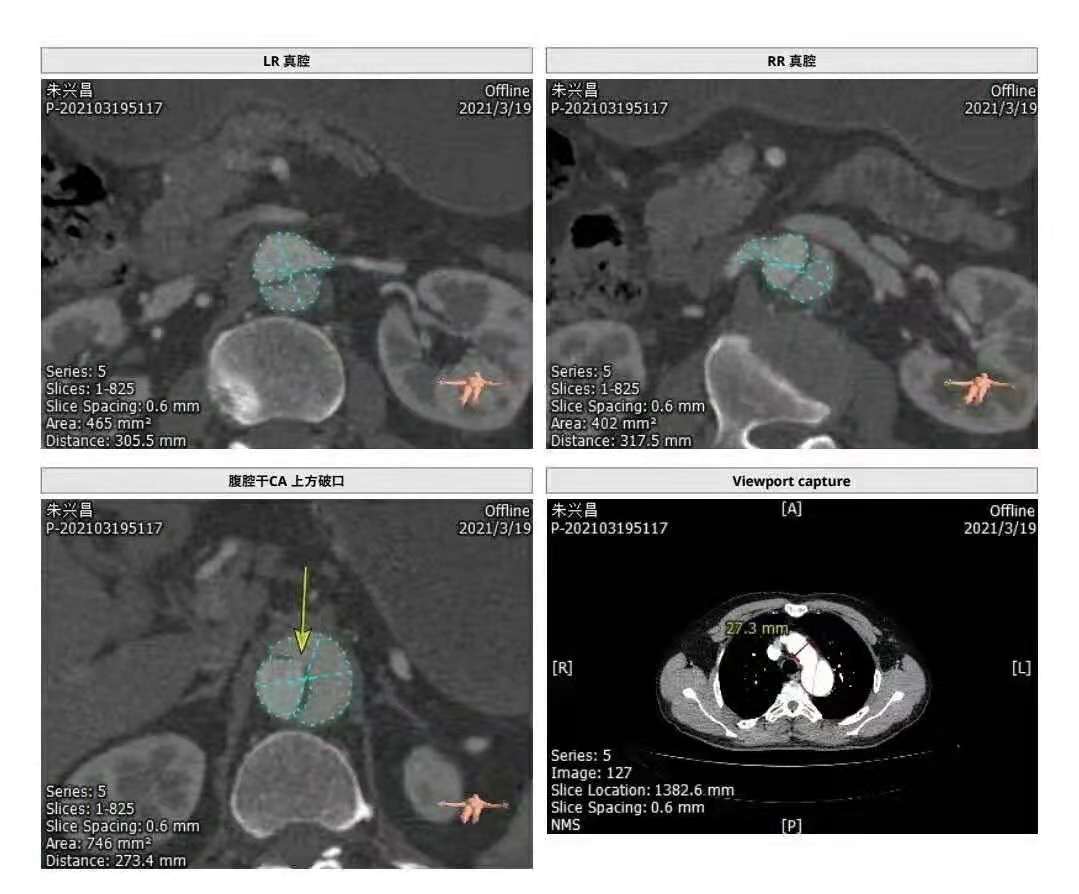

患者男性,67岁,因咳嗽、胸部不适就医,CT检查提示主动脉夹层(B型)、主动脉弓及腹主动脉硬化,局部形成钙化斑块,随以“主动脉夹层瘤”急诊收住。

时间就是生命,我院立即开辟绿色通道,以最快捷、最高效的就诊流程,积极完善术前准备,在局部麻醉下经腹股沟股动脉穿刺行“主动脉夹层腔内修复术”。西安交大一附院血管外科专家、主任医师冯骏教授亲临指导,手术顺利,破口封闭,血管真腔开通,整个手术过程历时约30分钟,患者生命体征稳定,术中、术后未诉不适;术后第二天,患者可下床活动;术后第三天,患者康复出院。